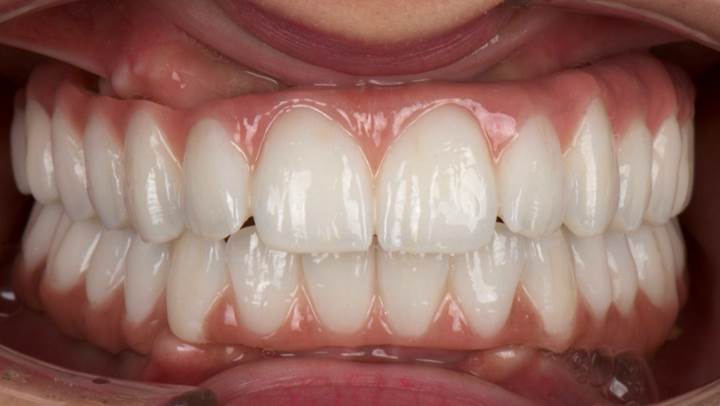

“AnyRidge ensures long-term biological stability

& functionality even in

full-mouth rehabilitation case. ”

Clinical case: Full-mouth implants for mandibular & maxilla - restored using mixed prostheses

- Courtesy of Dr. Hyun Jun Kim, Korea -

Keywords